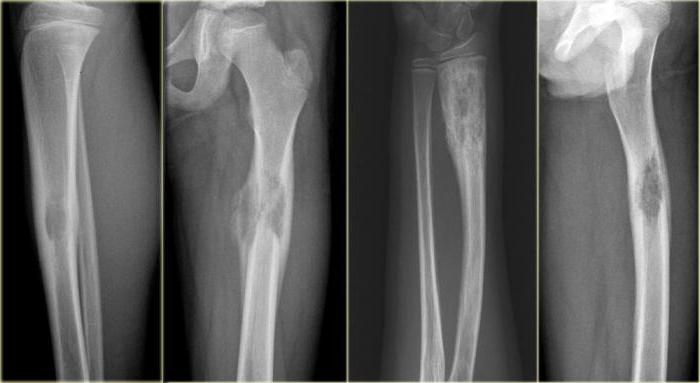

Рисунок 2. Эозинофильная гранулема кости: поражение бедра у девочки 11 лет (рентгенограмма). Отмечались припухлость и боль в течение 3 мес.

https://radiopaedia.org/cases/langerhans-cell-histiocytosis-skeletal-manifestations